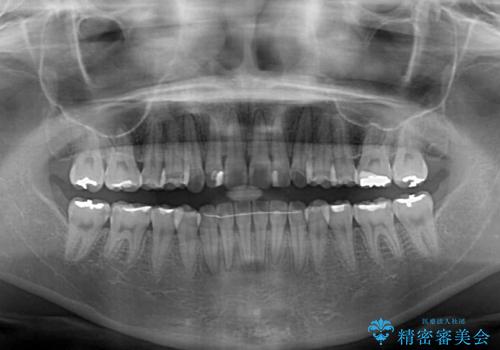

インビザライン適用の歯列であったため、歯と歯の間を削るIPRを用いて改善することとしました。

お仕事柄、長時間のマウスピース装着が苦ではなかったので、歯列はすぐに整いましたが、ゆっくりとした交換頻度であったので、2年ほどの治療期間を要しました。